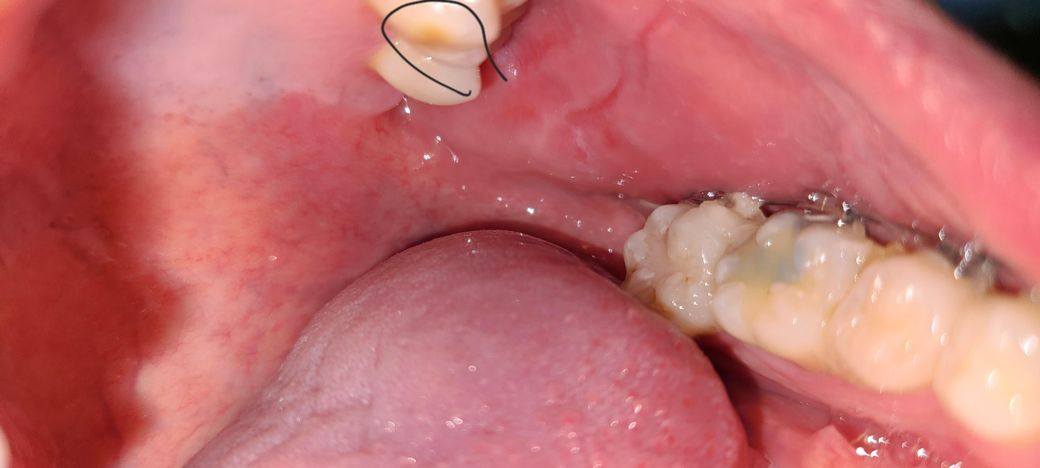

제 치아 사진인데 왼쪽 위 어금니 안쪽 사진인데 동그라미 친 곳에 갈색 점이 있는데 충치인지 확인 부탁드립니다. 사진첨부

제 치아 사진인데 왼쪽 위 어금니 안쪽 사진인데 동그라미 친 곳에 갈색 점이 있는데 충치인지 확인 부탁드립니다. 치과가기 전에 질문 드립니다.

• 1번 째 사진